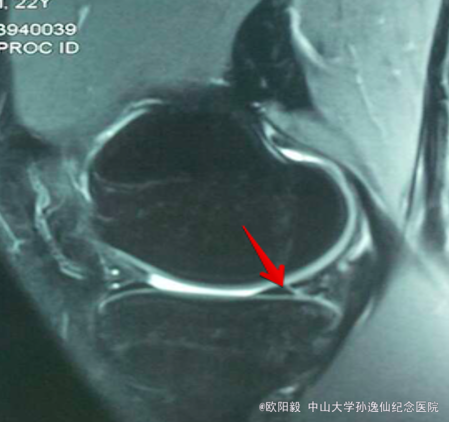

查体:双下肢无畸形,右膝关节关节间隙压痛,麦氏征(+),肢端血运、感觉、活动正常。左下肢及双上肢其余关节未见明显异常。MRI检查提示:右膝关节内侧半月板损伤。

诊断:右膝关节半月板损伤。予右膝关节镜检+半月板修补术,术后开始行股四头肌肌力训练及踝泵训练,术后定期门诊复诊并行主被动康复训练。